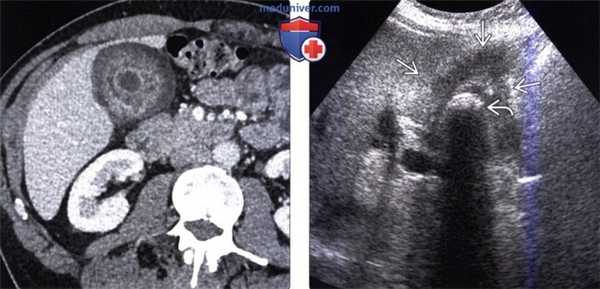

(Слева) На корональной КТ с контрастным усилением визуализируется полиповидное объемное образование (рак) в ампуле фатерова сосочка. Видна также часть билиарного стента ЕЕ. Изображения в корональной плоскости лучше всего позволяют визуализировать ампулу и оценить вероятное объемное образование.

(Справа) На корональной КТ с контрастным усилением визуализируется гиподенсное образование в ампуле, с нечеткими краями, вызывающие обструкцию общего желчного протока, при этом панкреатический проток расширен в незначительной степени. При оперативном вмешательстве был обнаружен рак ампулы фатерова сосочка.